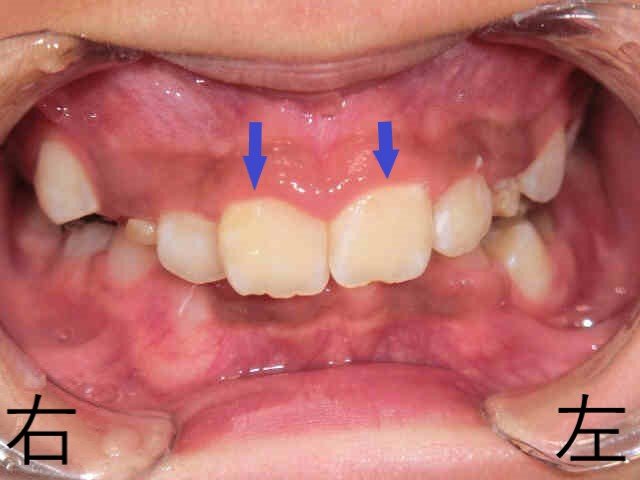

治療開始から12か月後(11歳6か月時)には、上下歯列の拡大が進行し、下顎の前下方への成長が確認されました。これにより、上顎前歯で隠れる下顎前歯の範囲が減少し、浅い噛み合わせが形成されつつあります。

しかし、当時はまだ混合歯列期であり、左右の上顎犬歯が正常な位置に萌出するかどうかが治療の鍵でした。

・ 11歳6か月時:上顎の拡大が進んでいたものの、左上乳犬歯が残存しており、犬歯の萌出スペースが不足